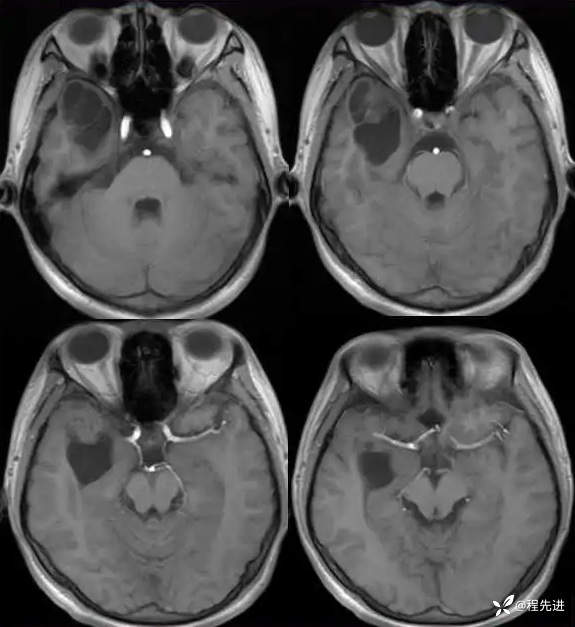

T1: